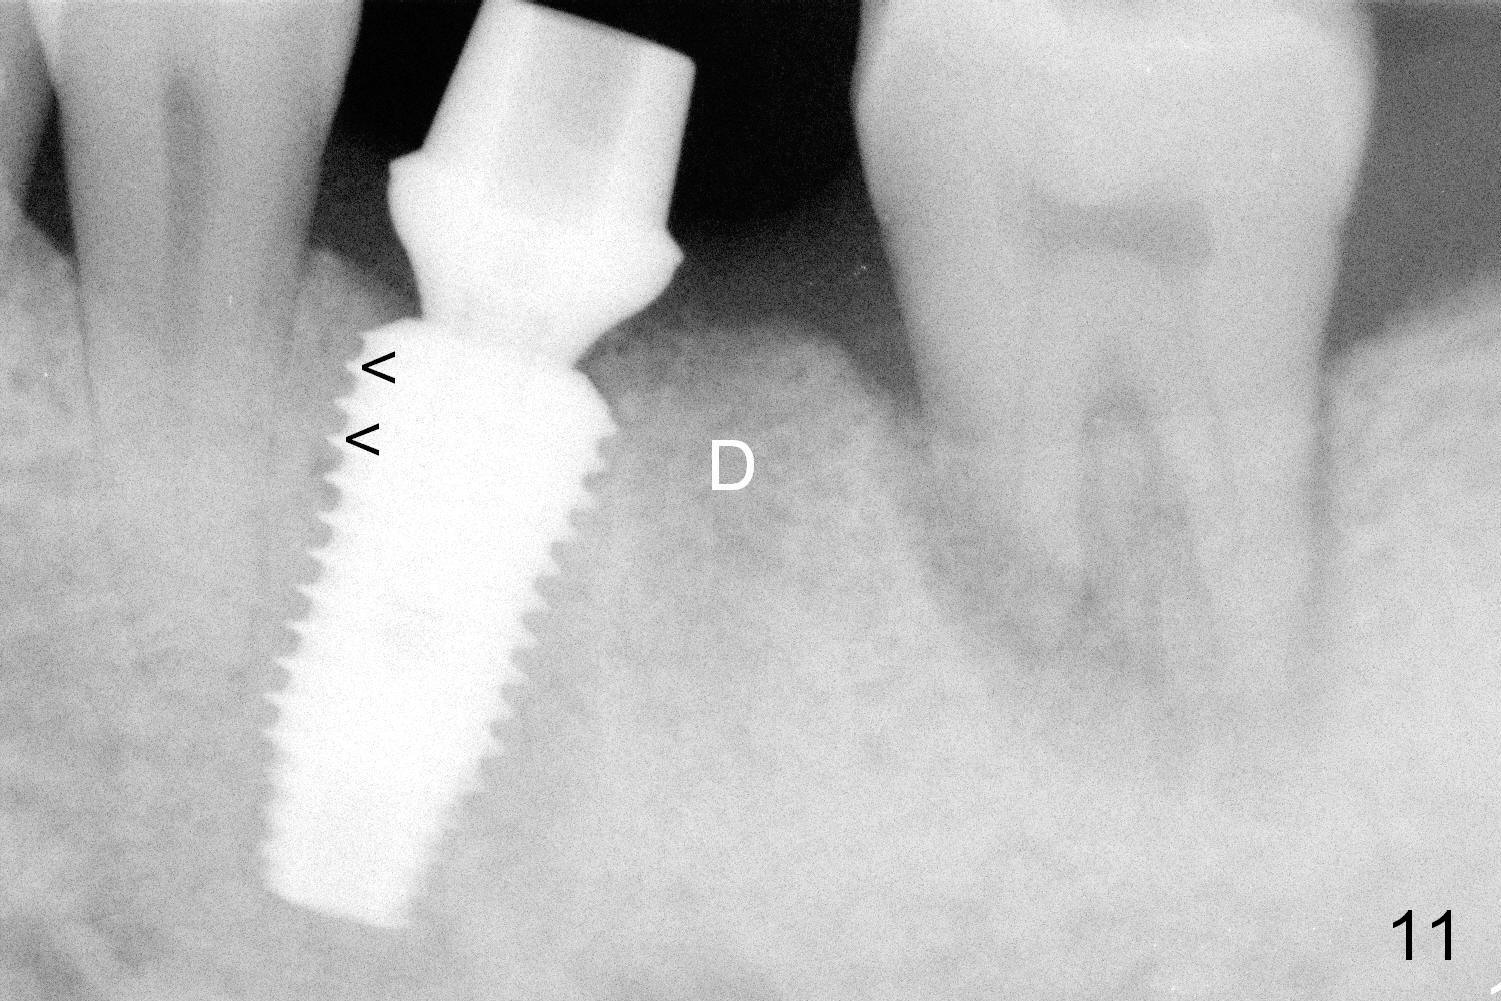

When the patient returns for final restoration 4 months postop, the soft tissue around the implant heals with distinct abutment margin (Fig.10). It is easy to take impression. This is due to the presence of the immediate provisional. The bone density in the original mesial (Fig.11 <) and distal (D) sockets increases, suggesting osteointegration. Eight months later (1 year postop (#19)), the tooth #18 becomes symptomatic and is extracted and replaced by an implant (Fig.12). The distal socket at #19 has disappeared, while the plateau of the implant is covered by the bone (^).